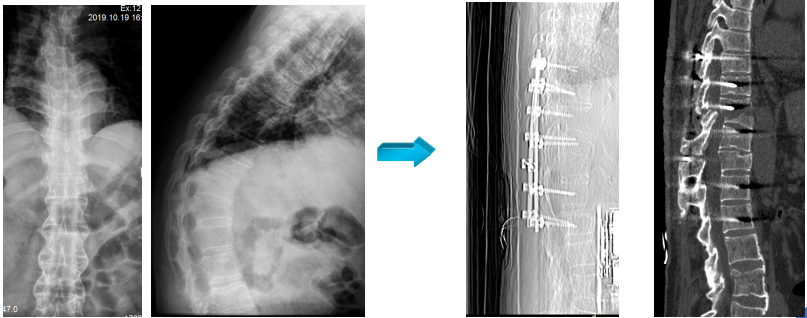

(二)开展了基于术中CT扫描结果微创治疗胸腰椎骨折技术

国内首次提出基于术中CT扫描精准、微创治疗胸腰椎骨折。

国内首家提出新理念,在COA、国际骨科会议上报道,得到国内专家的认可。

论文发表在中华医学杂志。

(三)基于术中CT治疗胸腰椎骨折

提出骨折块压迫脊髓出现神经症状不是绝对减压的指证,补充了胸腰椎骨折的治疗指南。

论文发表在《中华医学杂志》。